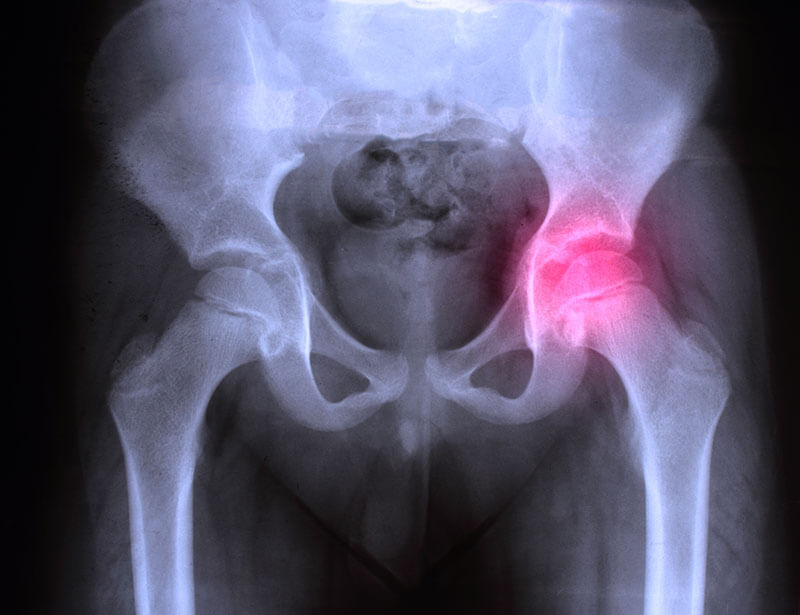

Diagnosticarea coxartrozei

Coxartroza poate fi diagnosticata de un medic practicant numai cu ajutorul radiografiilor. Examinarea ajuta la definirea gradului de dezvoltare a bolii si a etiologiei acesteia.Primul lucru de care trebuie sa tineti cont este calificarea medicului: este important pentru diagnosticarea bolilor. Destul de des, un specialist dezvolta planul de tratament al coloanei vertebrale uitand de examinarea articulatiilor soldului si pierzand astfel timp pretios.

- Examinarea cu raze X. Aceasta permite vizualizarea starii soldurilor si evidentierea simptomelor.